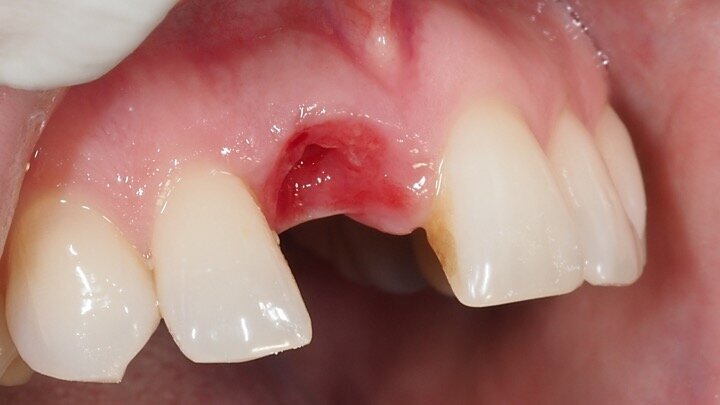

Figura 4. Exodoncia del diente.

Figura 5. Hundimiento de la zona estética anterior inmediatamente después de la extracción del diente por la reabsorción de la pared vestibular.